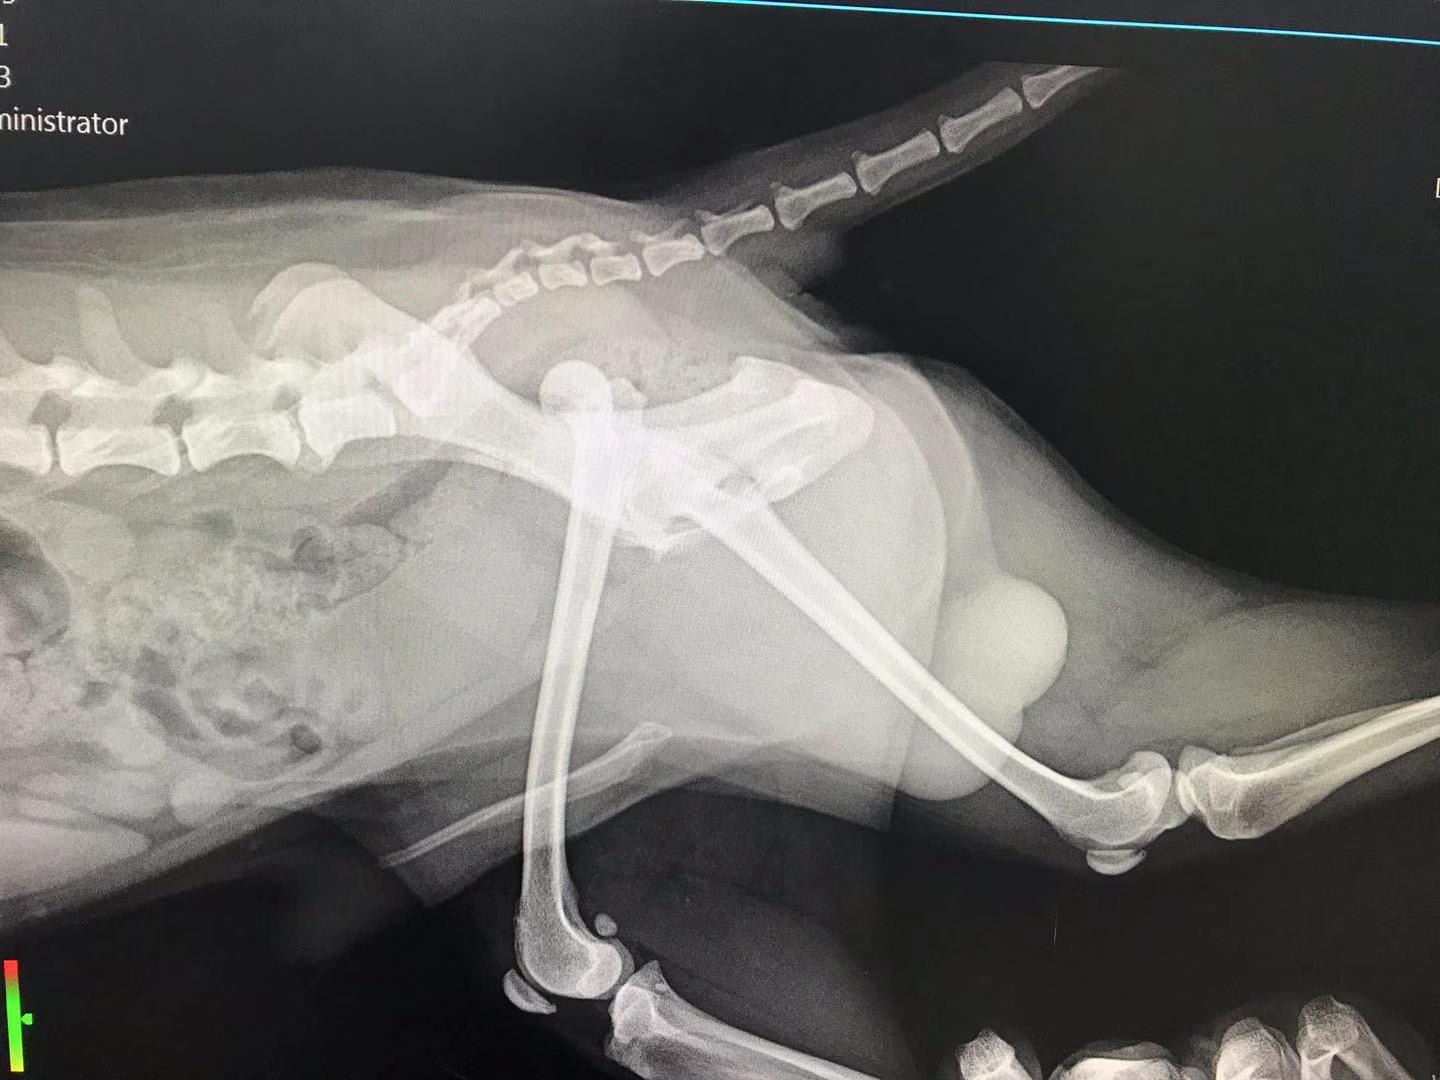

Hello, my dog is 8 years old now and he's facing two problems. The first one is patellar dislocation found two years ago and now it's the 3rd stage. Besides, he had a fight with a big dog 10 days ago, we took a X-ray today and found femoral ligament rupture. I'm wondering what treatment is best for him? Thank you very much.

Luxating patella is very common in small breed dogs. It can cause arthritis, and there is a surgery to address it if your vet tings Doudou is a good candidate. https://www.petcoach.co/article/luxating-patella/ As for the dislocated hip, he needs to surgery to replace it or to have the ball of the femur amputated (called a femoral head ostectomy - FHO). It sounds drastic, but is a very common surgery. The muscles of the hip/but will keep the joint in place, and, once healed, he should look completely normal when walking. You should discuss all available options with your vet, since the best one depends on the individual pet and their medical history. https://www.petcoach.co/article/5-most-common-orthopedic-injuries-in-dogs/